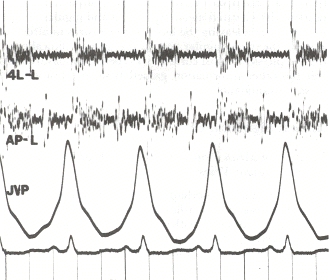

Other typical signs of pulmonary hypertension include an accentuated pulmonary component of the second heart sound, a right ventricular third heart sound, and parasternal heave indicating a hypertrophied right ventricle. Signs of systemic congestion resulting from right-sided heart failure include jugular venous distension, ascites, and hepatojugular reflux.[10][11][14] Evidence of tricuspid insufficiency and pulmonic regurgitation is also sought and, if present, is consistent with the presence of pulmonary hypertension.[10][11][15]